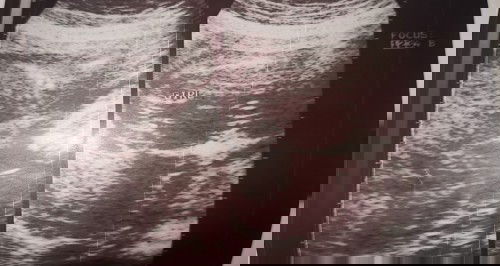

Date of birth:Dec.21,2020 Time of birth:2:00 am Normal Delivery #37weeksand3days My pink plane has already landed ❤️😍 Team January pero napaaga 😊😍Meet my baby Tiffany Skye 😘